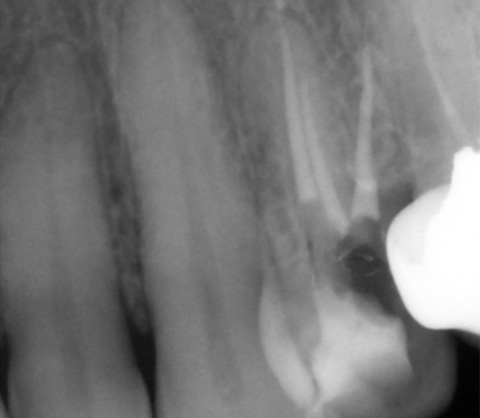

L'endodontie

L'endodontie est la partie de l'odontologie qui traite de l'intérieur de la dent. Elle consiste dans la prévention, le diagnostic et le traitement des maladies de la pulpe dentaire et des infections péri-apicales (dans l'os autour des racines).

Le dentiste réalise le traitement endodontique d'une dent lorsque celle-ci ne peut plus être gardée vivante, soit parce qu'elle est déjà nécrosée, soit parce qu'elle risque de le devenir.

- Bien nettoyer l'intérieur de cette dentracine, par une action mécanique : grattage de la surface intérieure des canaux pulpaires (à l'aide de limes endodontiques manuelles ou mécaniques), associée à une action chimique : irrigation avec de l'hypochlorite de sodium (eau de Javel diluée à 3 %), qui est le désinfectant le plus efficace

- Mettre en forme la lumière canalaire jusqu'au foramen apical, à l'aide de limes manuelles ou de limes mécanisées afin que la solution d'irrigation pénètre partout

- Réaliser l'obturation canalaire, le plus souvent à l'aide de gutta-percha chauffée ou froide, liée aux parois dentinaires avec un ciment canalaire.

Ensuite il faudra reconstituer la dent, soit avec une obturation coronaire si cette dent n'est pas trop délabrée, soit par une reconstitution prothétique (couronne) si elle est trop délabrée, afin d'assurer l'étanchéité du traitement et éviter que la racine ne soit recolonisée par les bactéries.